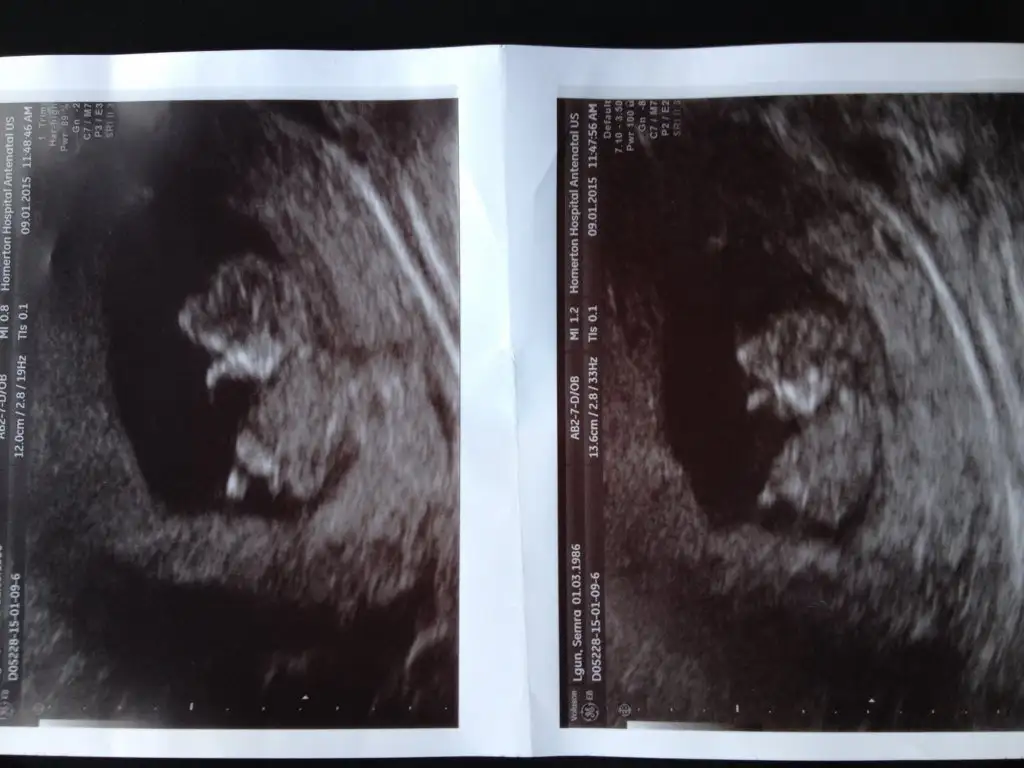

PrenssCvp için teşekkürler . Bide bu son fıtosu var ikiside çok farklı sznkiEki Görüntüle 1363266

On haftalık demişsin çok erken. Bu hafta kız erkek pek fark olmazki güzelim. Erkek geçti ama içimden erkege benzettim yani. Gönlüne göre olsun inşallahLütfen bi bakın çok merak ediyorum

Ben zaten çok anlamam tatlım Allah gönlüne göre versin inşallah. Ben de 18 haftada öğrenmiştim iki hafta daha merak et bakalim sonra net öğrenirsin. Beklemesi merak etmesi bile çok güzellSağol Cnm inş.. Radyoloji uzmanim bakmıştı bu ggörüntüler onun baktıkları içindendi kız demişti... Devletteki doğum dr u erkeğe benzetti bakalım inş iki haftaya belli olur o zaman randevum baya geç öğrenmiş olucam

On haftalık demişsin çok erken. Bu hafta kız erkek pek fark olmazki güzelim. Erkek geçti ama içimden erkege benzettim yani. Gönlüne göre olsun inşallah

Gıttim canım dayanamadım geçen Cumartesi sadece cinsiyet icin gıttım farklı bı doktora 100 dan söyledi ama ben Pazartesi zeka testı icin güdicem o zaman inanıcam ne olduguna kesin Pazartesi görüşürüzPelooooo Dr gitmedinmi sen meraklardsyim seni

Yanlış yazdım 100/ 90 tahmin ettiGıttim canım dayanamadım geçen Cumartesi sadece cinsiyet icin gıttım farklı bı doktora 100 dan söyledi ama ben Pazartesi zeka testı icin güdicem o zaman inanıcam ne olduguna kesin Pazartesi görüşürüz